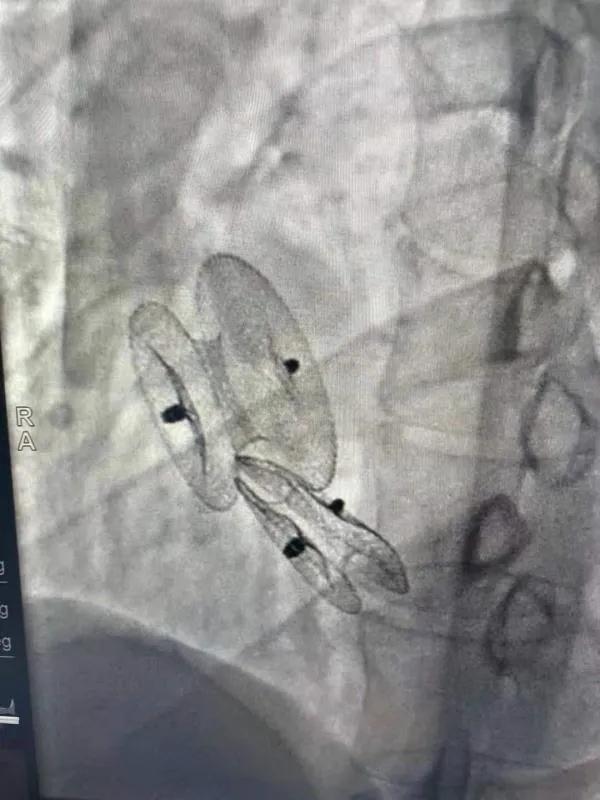

先天性心臟病房間隔缺損呈多孔型怎么辦?患者并非只能選擇開胸手術(shù)。近日,西安國際醫(yī)學(xué)中心醫(yī)院心臟病醫(yī)院成功開展一例雙孔房間隔缺損雙傘介入封堵術(shù)。

房間隔缺損是先天性心臟病的一種,介入手術(shù)相較于傳統(tǒng)的外科手術(shù)損傷小,風(fēng)險相對較低,術(shù)后恢復(fù)快。一般的房間隔缺損多呈單孔,封堵難度較小,而雙孔房間隔的封堵難度大大增加,至今僅有國內(nèi)頂尖的封堵專家成功完成了數(shù)例而已。

患者是位27歲的年輕女性,經(jīng)常感到心慌,心臟超聲發(fā)現(xiàn)房間隔缺損,并且房間隔缺損呈雙孔型,大的約14mm,小的約9mm,兩個缺損間相隔較遠(yuǎn),介入封堵難度非常大。

在詳細(xì)了解患者病情,仔細(xì)閱讀患者影像資料后,曾廣偉主任已經(jīng)有了清晰的手術(shù)策略。在精心的準(zhǔn)備和團隊的配合下,曾主任順利的利用兩個封堵器對房缺進行了封堵。